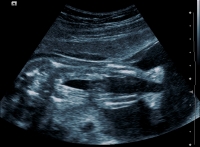

Głównym  celem badania w połowie ciąży jest wykrycie anomalii rozwojowych. Podczas  badania USG bardzo dokładnie zostanie oceniony płód, od czubka głowy, po stopy.

Ma to na celu szczegółową ocenę anatomii, położenia płodu, jego wzrastanie oraz ocena pępowiny, łożyska a także objętości wód płodowych.

Standardowo badanie w 20 tygodniu ciąży wykonywane jest w technice 2D. Jest to aktualnie metoda najdokładniejsza w wykrywaniu ewentualnych anomalii. Dodatkowo można wykonać badanie w technice 3D i 4D, co pozwala na trójwymiarową wizualizację płodu.

Badanie w drugim trymestrze trwa od 10 do 40 minut. Najczęściej pozwala na dokładną ocenę anatomii. Czasami warunki badania nie pozwalają na szczegółowe obejrzenie niektórych szczegółów anatomicznych. Niekorzystne położenie, zbyt duża ruchliwość płodu lub otyłość ciężarnej. W takiej sytuacji może zaistnieć konieczność powtórzenia badania.